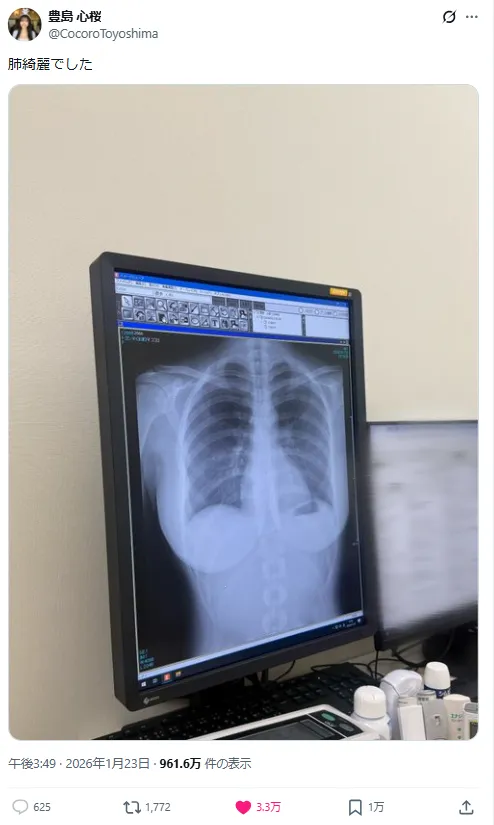

不过她23日早上于X贴出一张自己的胸部X光照片,却因为连X光照都可以清晰看出胸部线条,让这则贴文短短几个小时浏览数就冲破700万次,在网络上掀起热烈讨论。

她在贴文中表示,这是健康检查的结果,并轻松汇报“肺很干净”。不过,比起健康状况,照片中自然浮现的胸部线条反而成为焦点,可以看出她自豪的H罩杯轮廓。

引来大量网友吐槽与玩笑留言,像是“连 X 光都很色是怎样”、“这根本是天然巨乳吧”之类的幽默回应接连涌入。

甚至还有专业人士指出,从影像来看属于自然型胸部,再度成为话题加分项。不过没想到写真偶像居然连X光照片都可以引起话题,只能说这种好身材,连X光能崭露无遗,甚至还能宣传真材实料,真的是想都没想过吧。